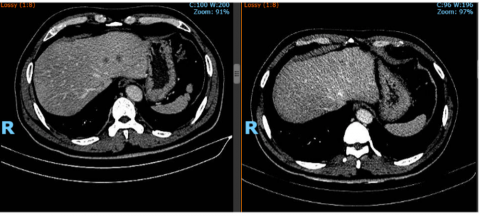

Bệnh nhân nam 58 tuổi, được chẩn đoán: Ung thư đại tràng di căn gan đa ổ đáp ứng

sau hóa trị phác đồ thuốc 6 tháng (các tổn thương di căn gan giảm kích thước

và số lượng sau hóa trị).